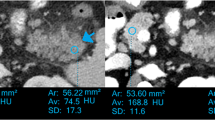

Image data measurement and quality score

Three sets of data were directly obtained from the portal phase dual-energy scan: 100 kV, Sn140 kV, and weighted-average 120 kV data. All were reconstructed as images with layer thickness of 1.5 mm and interlayer spacing of 1.0 mm. Additionally, 100 kV and Sn140 kV data were transmitted through a picture archiving and communication system to the Dual-Energy software of the Siemens Syngo MMWP VE36A Workstation, and the pancreatic parenchyma was delineated using the spectral information option in the monoenergetic program, obtaining the curve of iodine CNR against the energy level (keV) (Fig. 1). The image data for the CNR single-energy value was extracted. Next, the obtained 100 kV, Sn140 kV, weighted-average 120 kV, and the optimal CNR single-energy images (a total of four sets of images) were transferred into the Viewing window to manually delineate the regions of interest (ROI). On the 100 kV images, the ROI of pancreatic necrotic foci and of the adjacent pancreatic parenchyma without apparent necrosis were delineated, and the CT values in the ROI were measured. The CT value measurements of the other three groups of images were performed at the same level, the same site and in the same ROI. The pancreatic necrosis focal CT values (N values) and adjacent pancreatic parenchymal CT values (P values) were recorded separately for each group of images, followed by measurement of the standard deviation (SD value) of the fat CT value in the uniform fat area of the subcutaneous abdominal wall. The signal-to-noise ratio (SNR) of the pancreas was calculated using the pancreatic CT value/SD value, and the CNR of pancreatic parenchyma-necrosis was calculated with (P-N) value/SD value.